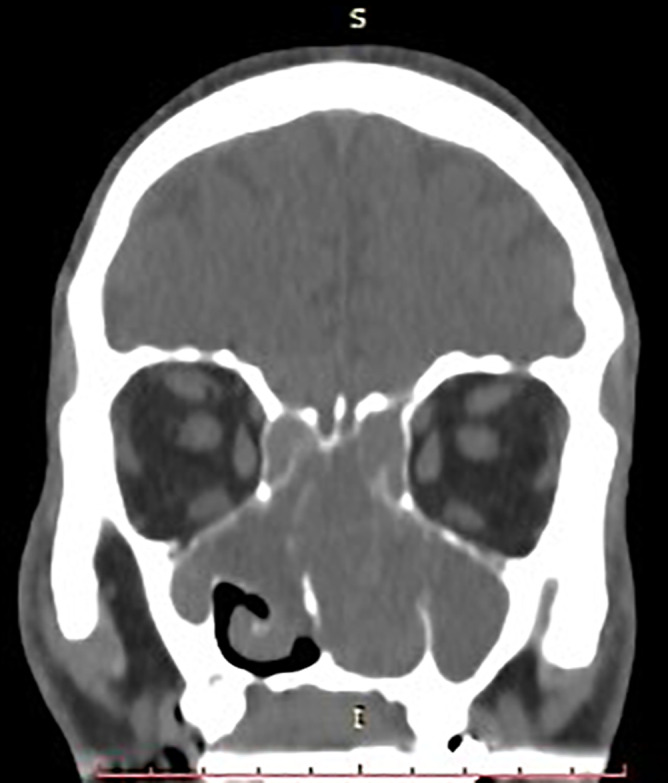

Case presentation: A 67-year-old male reported 10 months of nasal obstruction, mouth breathing, and sleep disturbances. The initial evaluation for foreign body obstruction revealed septal deviation and low-density sinonasal tissue on CT. MRI identified a 7 × 4.5 × 7 cm heterogeneous lesion invading nasal structures, paranasal sinuses, and nasopharynx with diffusion restriction. Tru-cut biopsy confirmed ACC via cribriform, tubular, and solid basaloid cell patterns, pseudocystic spaces, biphasic ductal-myoepithelial cells, and perineural invasion. Immunohistochemistry (CK7, CD117, p63, S100) supported the diagnosis, with tumor-free margins and no metastases. Multimodal therapy (30 VMAT sessions, 4 cisplatin-vinorelbine cycles) improved symptoms.

Abstract Image